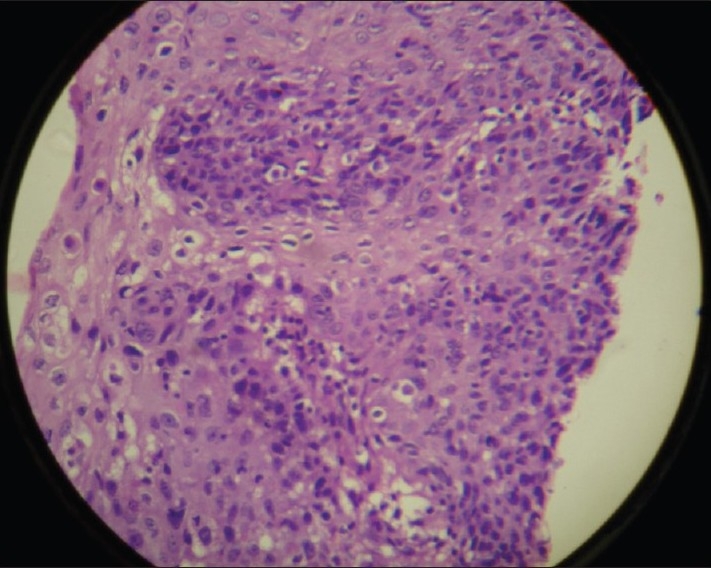

A 16-year-old female patient presented to the radiotherapy department in July 2008 with complaint of unrelenting hoarseness of voice for the last 1 year. She developed it gradually over a period of time. Initial treatment was directed to common cold but was of no help. There was no associated sore throat, otalgia, localized pain or tenderness over thyroid cartilage, dysphagia or features of airway obstruction. The patient is a nonsmoker and is nonalcoholic and without any history of past or present marijuana smoking. There was no history of prior neck irradiation. An incidence of cancer in the family could not be elicited from a detailed history. An indirect laryngoscopy was performed, which showed both vocal cords to be mobile. There was no visible growth over any of the vocal cords. Contrast-enhanced CT scan of the neck was performed, and it showed a small irregular lesion over the left vocal cord at the junction of anterior one third and posterior two thirds [Figure 1]. Thickening of left true vocal cord with loss of paraglottic fat is seen, suggestive of a neoplastic lesion. The normal paraglottic fat on the right side is seen as black area just deep to the thyroid cartilage (seen as white). The airway is seen as black oval structure. There is no visible neck node. Fiber-optic laryngoscopy confirmed the CT scan finding, which also showed irregular lesions along the medial margin of the left vocal cord [Figure 2]. Both CT scan and fiber-optic laryngoscopy showed an otherwise normal picture. Microlaryngoscopic removal of the mass was performed. Histopathological examination under low-power and high-power fields showed severe dysplasia and full-thickness replacement of epithelium with dysplastic cells and diagnosed it as carcinoma in situ [Figures [Figures33 and and4].4]. However, the risk of a micro-invasive carcinoma could not be ruled out. A second biopsy was advised to obtain deeper tissue, but it was refused by the patient. So from the available documents, we considered it carcinoma in situ of the vocal cord.

| Figure 1 CECT scan of neck showing irregular lesion along the medial margin of left vocal cord at the junction of anterior one third and posterior two thirds. There is thickening of left true vocal cord with loss of paraglottic fat, suggestive of a neoplastic lesion. The normal paraglottic fat on right side is seen as black area just deep to the thyroid cartilage (seen as white). The airway is seen as black oval structure